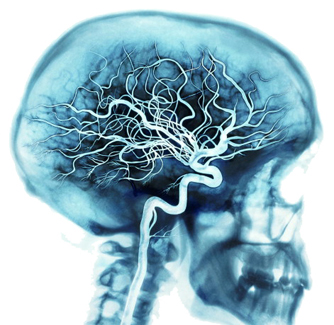

2. Rete di alimentazione

Il nostro cervello è alimentato da una delle reti più ricche di vasi sanguigni presenti nel nostro corpo.

Ad ogni battito cardiaco, le arterie portano circa il 20-25 percento del nostro sangue al cervello, dove miliardi di cellule impiegano circa il 20 percento dell'ossigeno e alimentano i vasi sanguigni.

Quando pensiamo intensamente, il cervello può usare fino al 50 percento di energia e ossigeno.

L'intera rete si vasi sanguigni è costituita da arterie, vene e capillari.